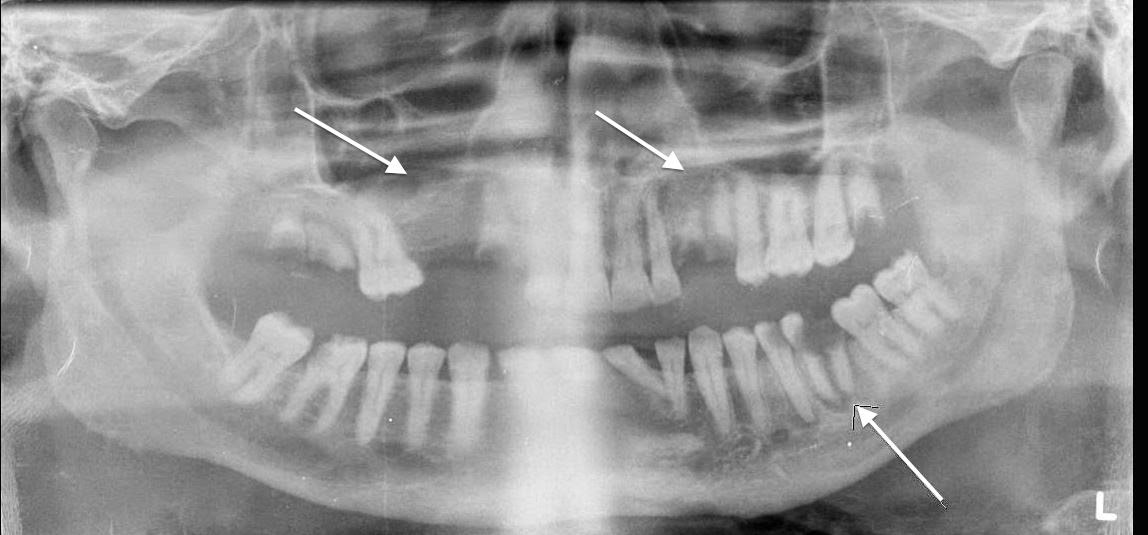

abscess periapical radiograph molar mandibular diffuse radiolucency root acute distal intraoral exostosis torus maxillary palatinus arrows sinus.